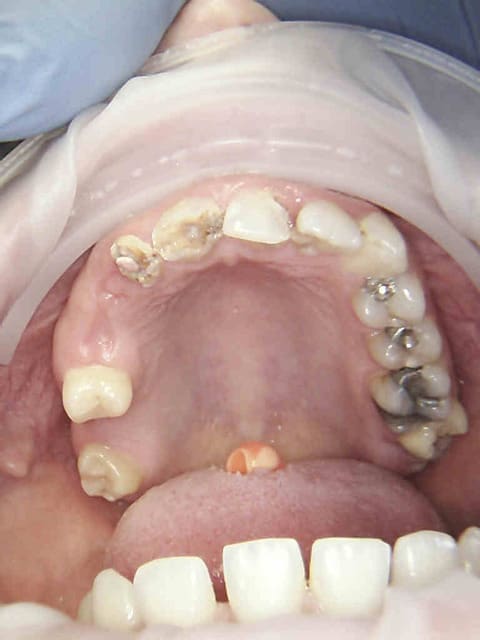

RDV d'une demi-heure initialement consult. légère gène sur 26 (tu m'étonnes). Radio de 26, anesthésie, status (antécédents de soins intensifs) detartrage, extraction. 5 mn pour le det, 2 mn pour l'extrac.

Sinon ca en RDV de 2H endo (R40 pour une fois) taille, empreinte, provisoires( dont un café et 2 tours sur eugenol) terminé en 1H 30, tu fais pas non plus ? -)))))

Le petit chicot au pays de la CCAM a encore frappé. -)))))

heu enlaye , on ne discute pas les travaux de chicot ! Sinon il ne va plus publier et alors là ce sera le désert total .. Bon tes endo , je ne suis pas sure que tridimensionnellement ... mais bon je chipote là , t'as mis la digue , tout va bien ..non ? waouh alors là,vu l'état buccal de la nana , tu cours à la cata . mais c'est vrai pour 2000 € , ça vaut pas le coup de se faire c.....